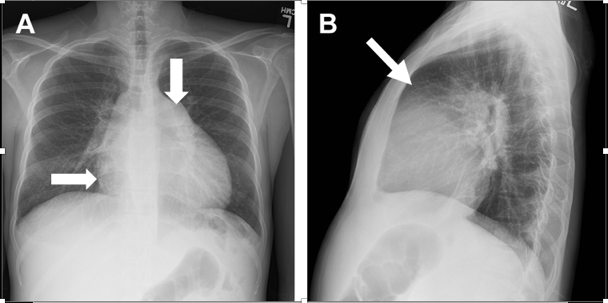

- Chest xray with enlarged right heart border, enlarged pulmonary artery shadow, and obliteration of the retrosternal space

- CT chest can suggest PH (size of pulmonary artery >30mm, enlarged RV, pulmonary artery > proximal ascending aorta) (4; 5)